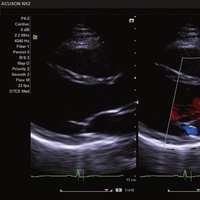

• 2D M-Modus

• M-Color-Flow Modus

• Anatomischer M-Modus

• Trapezoider M-Modus

• Color, Power Angio, PW (Pulse Wave) Doppler

• SCW-Doppler

• Live 3D / 4D OBS/GYN

• Stress Echo

• HD Live

• Tissue Doppler Imaging

• Tissue Harmonic Imaging

Das ACUSON NX2 Ultraschallsystem besitzt eine zukunftsfähige digitale Plattform mit nahezu unerreichter Bildqualität und sorgt für effiziente und zuverlässige Diagnosedaten. Die Vielseitigkeit des Ultraschallsystems wird mit einem großen kompatiblen Portfolio an Schallköpfen gedeckt, und so ist für jeden Anwendungsbereich etwas dabei. Die Bedienkonsole ist intuitiv aufgebaut und optimiert und erlaubt bis zu vier nach vorne gerichteten Schallkopfanschlüssen für eine enorme Effizienz und schnellen Workflow. So lassen sich bei der fetalen Bildgebung außergewöhnlich detailgetreue Darstellungen des Fetus im Gesicht zeigen oder durch die herausragende Farbdopplersensitivität bei der Darstellung der kleinen Gefäße des zystischen Schilddrüsenknotens kleinste Details erkennen. Weiterhin besticht das NX2 mit einfacher Aufrüstbarkeit bei wachsenden Anforderungen für Ihre zukünftigen Anwendungen und kompatible skalierbare Schallköpfe verringern ihren Kapitaleinsatz um bis zu 31 %.